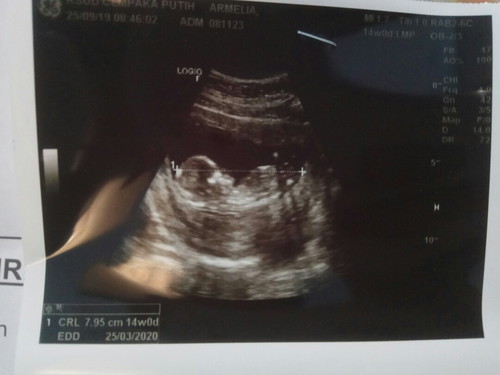

Kemaren sempet panik karna kemaren keluar flek banyak banget, usia kandunganku 14w Tapi tadi USG Alhamdulillah kata dokternya bentuk janinnya udah jelas banget, djj juga normal dan kata dokter ini anak aktif banget enggak bisa diem gerak terus?? Kemungkinan kata dokter keluar flek kemaren karna kecapean aja Lega rasanya denger penjelasan dokter dan terharu juga pas tadi usg si dede aktif banget dan ngerti banget kayanya kalo lagi ditengokin sama bunda dan ayahnya?? Sehat terus ya nak jangan bikin bunda dan ayah panik terus??❤❤❤